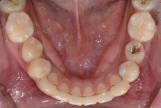

앞니 덧니, 전체치열 후방이동, 치간삭제 (20대 여성)

앞니 덧니로 교정치료를 시작하셨습니다. 덧니를 고르게 하면서 앞니가 앞으로 뻐드러지지 않도록 미니스크류를 이용하여 전체 치열을 후방 이동 시켰습니다. 당신의 미소를 생각합니다, 교정전문 서울바른이치과